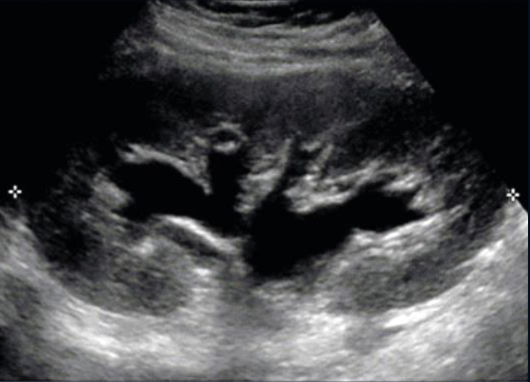

What is this?

Moderate Hydronephrosis (As it is one coherent structure there is not segmented Echogenic Structures)